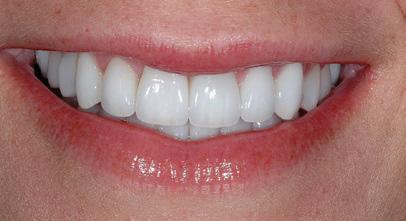

There Is Only One Smile That Matters. Yours!

You are in good hands! Dr. Makarita is the only accredited Fellow of the American Academy of Cosmetic Dentistry in Virginia.

BEFORE AFTER

At Tysons Aesthetic Dentistry Dr. Makarita has designed and equipped his practice with your smile in mind. Dedicated care and attention are just the beginning.

As a general dentist with a passion for aesthetic and cosmetic dentistry, whether a simple filling or a smile makeover, Dr. Makarita’s priority is to help you love your smile.

Since earning his doctorate from the Medical College of Virginia, Dr. Makarita has continually upgraded his skills and knowledge with continuing education so he can always bring you the most advanced options for all your dental needs.

Always welcoming new patients! Call 703-532-2020  8150 Leesburg Pike | Suite 503, Vienna VA 22182 www.ilovethatsmile.com

FREE SMILE EVALUATION In person or visit website for virtual smile consultation

Dr. H.R. Makarita

Accredited Fellow, American Academy of Cosmetic Dentistry

Master, Academy of General Dentistry

Master, International Congress of Oral Implantologists

to Love Your Smile? Dr. Makarita would love to meet you! About